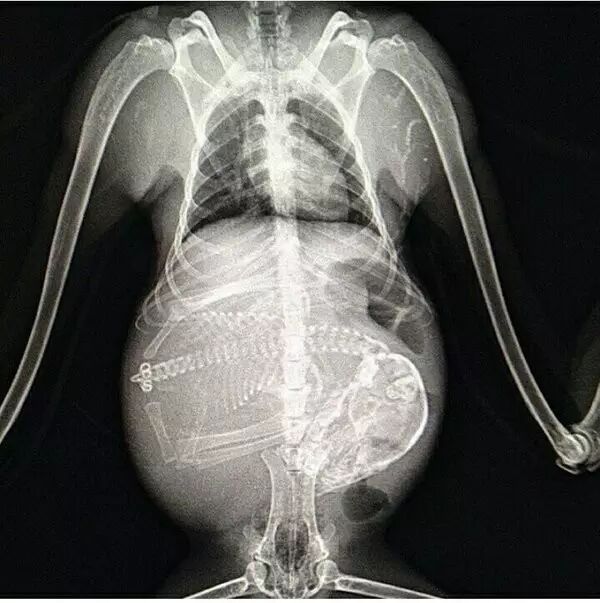

1. 狗狗。

能数得出是几胞胎吗?

据说这张X光照片是马和狗交配后的胎儿,可能是一张假照…